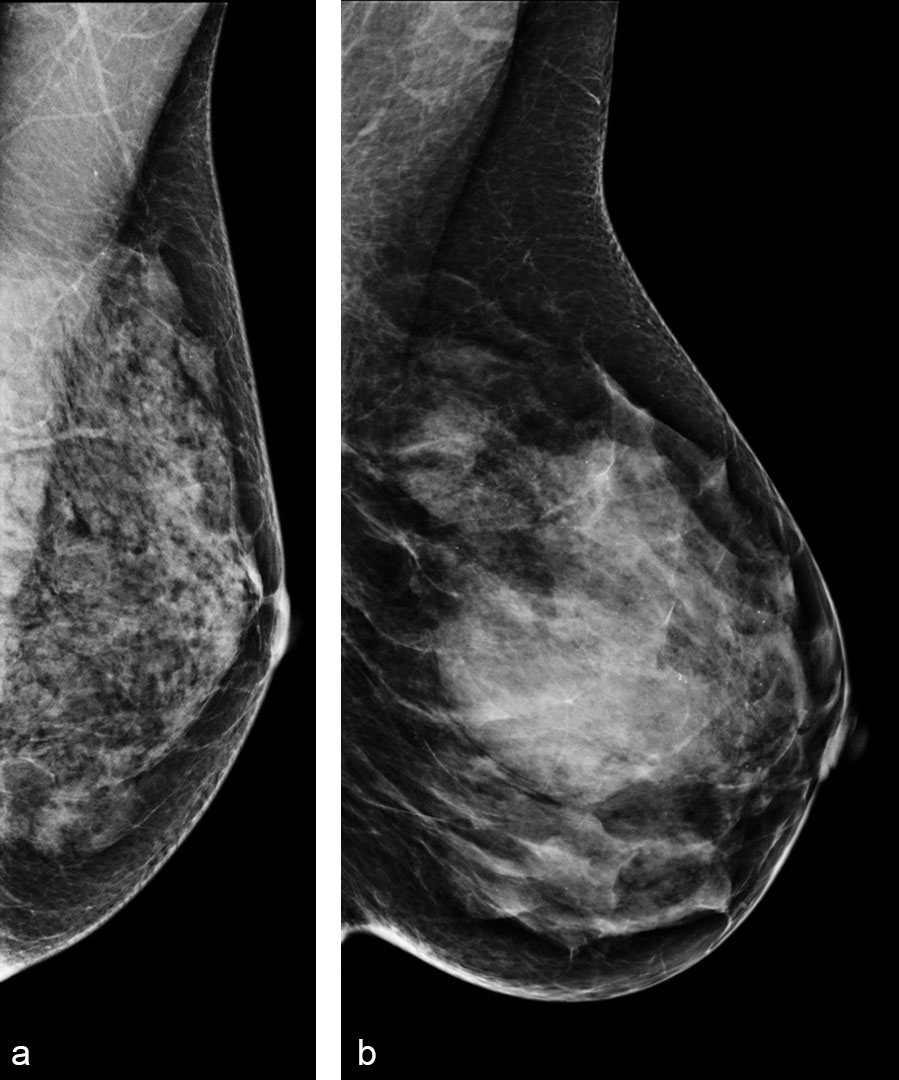

Images show examples of negative digital screening mammograms of women with (a) high density and high complexity (percent density [PD], 42%; complexity score [CS], 0.6), (b) high density and low complexity (PD, 43%; CS, 20.6). Corresponding age and body mass index for these women were (a) 54 years and 19.5 kg/m2, (b) 46 years and 28.7 kg/m2. Kontos, et al, Radiology 2018 © Radiology 2019